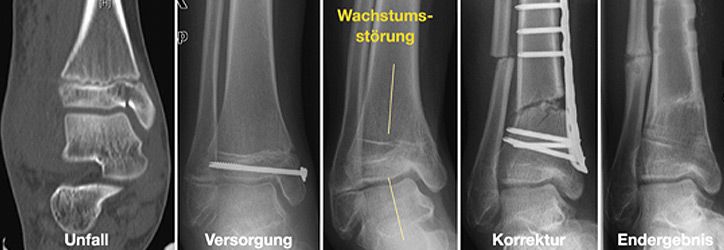

Für die Behandlung von Knochenbrüchen im Kindesalter sind genaue Kenntnisse des Wachstums nötig. Knochenbrüche können das Wachstum hemmen, überschießen oder fehlleiten. Andererseits können Fehlstellungen in bestimmten Grenzen alleine durch Wachstum korrigieren werden. Somit sind für eine Therapieentscheidung die Faktoren Patientenalter, Fehlstellungsausmaß und Korrekturpotenz von größter Bedeutung.

- Operative Korrekturen von fehlverheilten Knochenbrüchen

Korrekturoperation

Nur selten treten Wachstumsstörungen oder Verheilungen in Fehlstellung auf. Um dennoch eine volle Belastung und uneingeschränkte Beweglichkeit zu gewährleisten, führen wir entsprechende Korrekturoperationen durch.